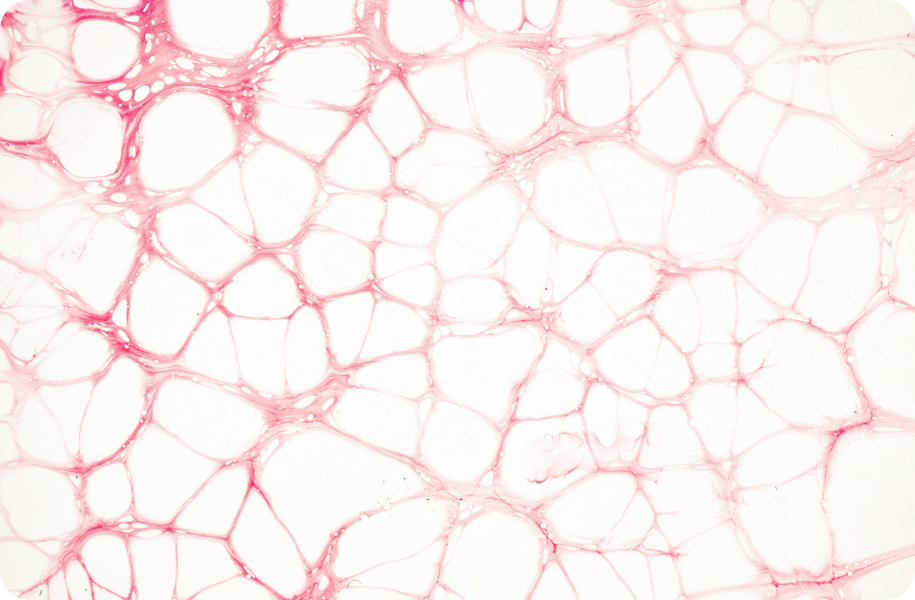

Стовбурові клітини – це, так би мовити, первинні, недиференційовані клітини, властиві всім багатоклітинним організмам. Стовбурові клітини підтримують свою популяцію за рахунок постійного поділу та мають здатність диференціюватися в клітини інших тканин організму. У 1960 році цей тип клітин відкрили канадські вчені і почалося їхнє широкомасштабне дослідження. Головними джерелами стовбурових клітин є кістковий мозок та пуповинна кров.